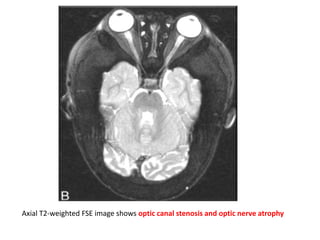

Severe bilateral optic canal narrowing (arrows) in a 4-yr-old patient with

complete loss of vision in the left eye and 20/80 visual acuity in the right eye.

Axial T2-weighted FSE image shows optic canal stenosis and optic nerve atrophy